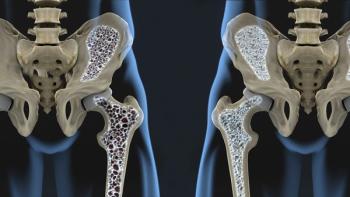

X-rays show that patients with osteoarthritis who receive a hip steroid/anesthetic injection may develop osteonecrosis of the hip.